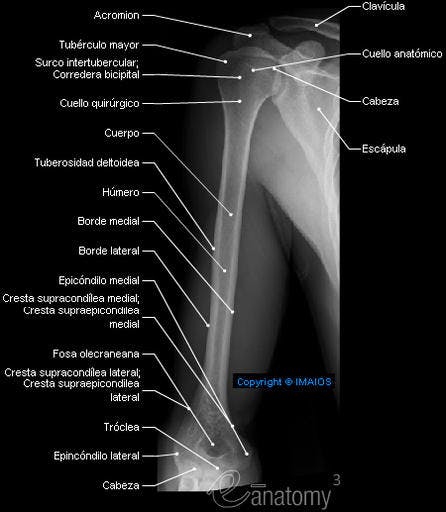

HUMERO

El húmero (en latín, humerus) es un hueso largo que forma parte del esqueleto apendicular superior y que está ubicado exactamente en la región del brazo.

Se articula a superior con la escápula, por medio de la articulación del hombro (o articulación glenohumeral) y a inferior con el cúbito y con el radio, por medio de la articulación del codo (o articulación humeroradioulnar).

DIAFISIS DEL HUMERO

Cuerpo o diáfisis: el cuerpo es cilíndrico en su parte proximal y a medida que se aleja es más triangular y plano.

Esta formado por tres caras y tres bordes, y se separa de la epífisis superior por el cuello quirúrgico del húmero.

El cuerpo del húmero se encuentra rotado , formando el canal de torsión del húmero por donde transcurre el nervio radial y la arteria humeral profunda.

EPIFISIS PROXIMAL (CABEZA HUMERAL) Y EPIFISIS DISTAL DEL HUMERO

La cabeza del húmero se encuentra en la epífisis proximal.

Bajo la superficie articular se presenta un estrechamiento que corresponde al cuello anatómico , cuya disposición es oblicua y que se ubica sobre los tubérculos mayor y menor del hueso. También presenta un cuello quirúrgico , corresponde a un sitio común de fractura.

El tubérculo mayor (llamado troquiter) posee una disposición de dirección posterolateral. El tubérculo mayor se continua hacia distal con la cresta del tubérculo mayor .

El tubérculo menor (llamado troquín) posee una disposición hacia anterior y sirve para la inserción del músculo subescapular. El tubérculo menor se continua hacia distal con la cresta del tubérculo menor. .

– La epífisis distal corresponde al cóndilo del húmero . El capítulo del húmero ( conocido de manera clásica como cóndilo humeral), ubicado a lateral, corresponde a la superficie articular que se relaciona con la fosita articular del radio. La tróclea del húmero ( ubicada a medial, corresponde a la superficie articular que se relaciona con la escotadura troclear del cúbito.

– La fosa coronoidea , ubicada a medial y a anterior, recibe a la apófisis coronoides de la ulna (cúbito).

– La fosa del olécranon, ubicada a posterior, recibe al olécranon de la ulna. El capítulo del húmero es una eminencia redondeada y lisa. Se articula con la fosita de la de la cabeza del radio.

– La fosa radial, ubicada a lateral y a anterior, recibe a la cabeza del radio.

EMINENCIAS ARTICULARES DEL HUMERO EN LA ARTICULACIÓN DEL CODO

Eminencias no articulares: son la epitróclea y el epicóndilo , ambos son la superficie de inserción de los músculos del antebrazo.

– Epicóndilo lateral ó epicóndilo: redondeado , se encuentra por encima del cóndilo humeral, donde se inserta el ligamento lateral externo de la articulación del codo y de los músculos epicondileos.

– Epicóndilo medial ó epitróclea: tuberosidad superomedial a la tróclea. Es una eminencia triangular, ubicada por encima de la tróclea.